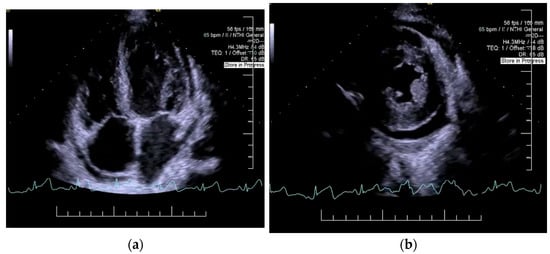

2. Case Presentation